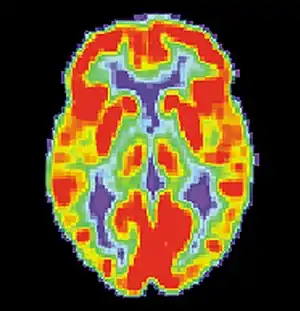

Human immunodeficiency virus (HIV)

Neural systems used by procedural memory are commonly targeted by Human Immunodeficiency Virus; the striatum being the structure most notably affected.[64] MRI studies have even shown white matter irregularity and basal ganglia subcortical atrophy in these vital areas necessary for both procedural memory and motor-skill.[65] Applied research using various procedural memory tasks such as the Rotary pursuit, Mirror star tracing and Weather prediction tasks have shown that HIV positive individuals perform worse than HIV negative participants suggesting that poorer overall performance on tasks is due to the specific changes in the brain caused by the disease.[66]